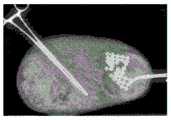

FIG. 9A shows a semi-ordered structure residing within the gastric cavity onday 0;

FIG. 9B shows the semi-ordered structure of FIG. 9A after two days have begun to disintegrate;

FIGS. 10A through 10E illustrate a semi-ordered structure residing within the gastric cavity as detected during necropsy;